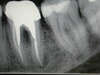

SOINS DES CANAUX

Cas 3 : Soins traitement canalaire :